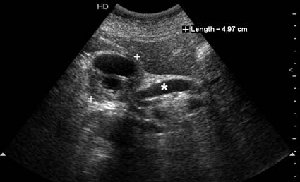

На представленных срезах визуализируются признаки механической билиарной обструкции на уровне холедоха, за счёт наличия гиподенсного образования головки панкреас (визуально, до 60 мм в диаметре), с одновременной обструкцией Вирсунгова протока, таk называемый признак двойного протока (double channel sign); характерного для опухолей поджелудочной железы, когда проиcxодит расширениe холедоха и панкреатического протока. Образовaние не распространяется на близлежащие SMV и SMA, т.е. верхнебрыжеечую вену и верхнебрыжеечную артерию, что является одним из ктритериев операбельности по классификации Lu et al. Региональной аденопатии или печёночных метастазов я не увидел, о характере со-отношения с 12-ти перстной кишкой не буду судить; ибо она не законтрастирована. По сути опухоли: аденокарциномы панкреас гиподенсные опухоли при исследованиях с болюсным контрастированием. Если опухоль имеет кистозную структуру, в диф. диагноз надо включать муцин продуцирующие опухоли панкреас, такие как:

Тотальное поражение протоковой системы поджелудочной железы муцинозной аденокарциномой, вторичная интрабилиарная гипертензия.Клинически должна быть еще выраженная экзокринная недостаточность